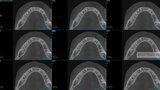

Fig.2a: Pre-op CBCT images of tooth #46: No obturation material in the distal and mesiobuccal canal (a); scanty obturation of the canals and breach of the floor of the pulp chamber, no obturation beyond a few millimetres down the orifice (b & c); radiolucency in the furcation area and periapical region of both roots (d -g).

Fig.2b: Pre-op CBCT images of tooth #46: No obturation material in the distal and mesiobuccal canal (a); scanty obturation of the canals and breach of the floor of the pulp chamber, no obturation beyond a few millimetres down the orifice (b & c); radiolucency in the furcation area and periapical region of both roots (d -g).

Fig.2c: Pre-op CBCT images of tooth #46: No obturation material in the distal and mesiobuccal canal (a); scanty obturation of the canals and breach of the floor of the pulp chamber, no obturation beyond a few millimetres down the orifice (b & c); radiolucency in the furcation area and periapical region of both roots (d -g).

Fig.2d: Pre-op CBCT images of tooth #46: No obturation material in the distal and mesiobuccal canal (a); scanty obturation of the canals and breach of the floor of the pulp chamber, no obturation beyond a few millimetres down the orifice (b & c); radiolucency in the furcation area and periapical region of both roots (d -g).

Fig.2e: Pre-op CBCT images of tooth #46: No obturation material in the distal and mesiobuccal canal (a); scanty obturation of the canals and breach of the floor of the pulp chamber, no obturation beyond a few millimetres down the orifice (b & c); radiolucency in the furcation area and periapical region of both roots (d -g).

Fig.2f: Pre-op CBCT images of tooth #46: No obturation material in the distal and mesiobuccal canal (a); scanty obturation of the canals and breach of the floor of the pulp chamber, no obturation beyond a few millimetres down the orifice (b & c); radiolucency in the furcation area and periapical region of both roots (d -g).

Fig.2g: Pre-op CBCT images of tooth #46: No obturation material in the distal and mesiobuccal canal (a); scanty obturation of the canals and breach of the floor of the pulp chamber, no obturation beyond a few millimetres down the orifice (b & c); radiolucency in the furcation area and periapical region of both roots (d -g).